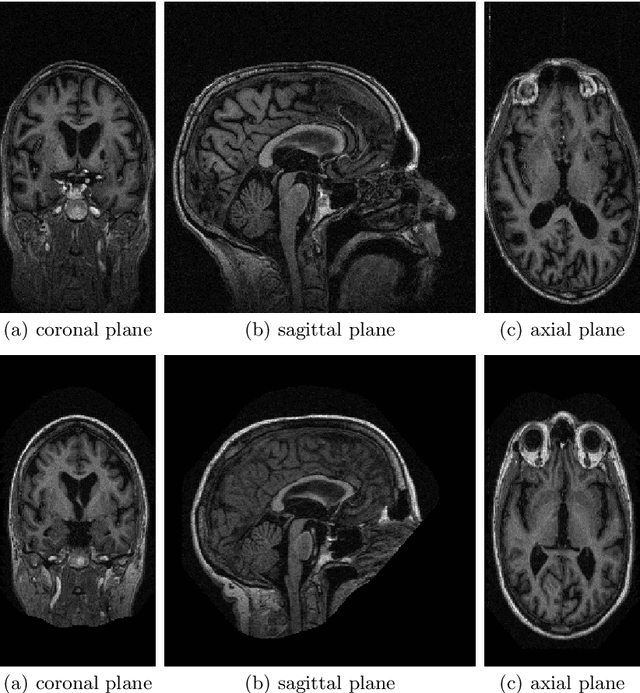

Abstract:The primary goal of this work is to study the effectiveness of an unsupervised domain adaptation approach for various applications such as binary classification and anomaly detection in the context of Alzheimer's disease (AD) detection for the OASIS datasets. We also explore image reconstruction and image synthesis for analyzing and generating 3D structural MRI data to establish performance benchmarks for anomaly detection. We successfully demonstrate that domain adaptation improves the performance of AD detection when implemented in both supervised and unsupervised settings. Additionally, the proposed methodology achieves state-of-the-art performance for binary classification on the OASIS-1 dataset.